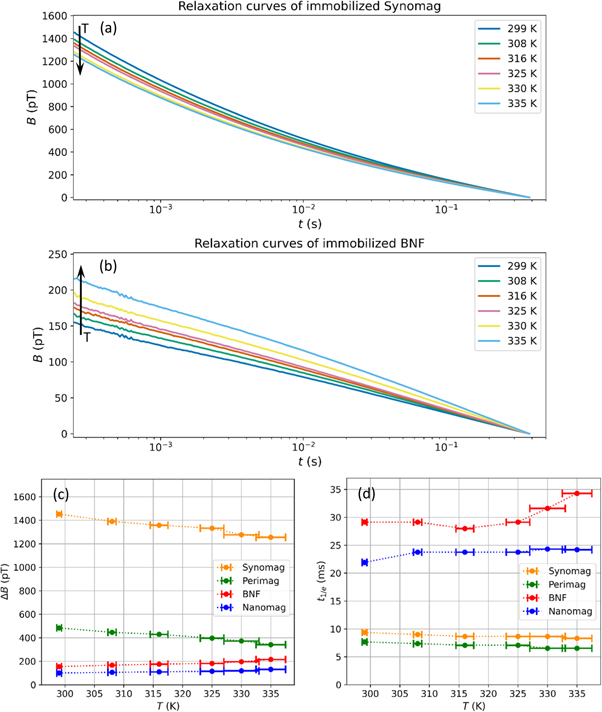

The relaxation signals of immobilized Synomag and BNF at different temperatures from 299 to 335 K are shown in figures 4(a), (b). As can be seen, the signals of the samples behave differently by increasing temperature. For Synomag and Perimag, the ΔB decrease by about 13% and 29%, respectively, and their  shorten with increasing temperature, see figures 4(c), (d). However, BNF and Nanomag show opposite behaviour; their ΔB values increase by about 28% and 23%, respectively, and their

shorten with increasing temperature, see figures 4(c), (d). However, BNF and Nanomag show opposite behaviour; their ΔB values increase by about 28% and 23%, respectively, and their  values become longer with rising temperature. Again, Synomag shows the least change. Repeating the measurements under nominal identical conditions revealed that changes in ΔB for the highest temperatures of fluid and immobilized samples are below 8%, indicating that the effect of temperature on ΔB is substantial.

values become longer with rising temperature. Again, Synomag shows the least change. Repeating the measurements under nominal identical conditions revealed that changes in ΔB for the highest temperatures of fluid and immobilized samples are below 8%, indicating that the effect of temperature on ΔB is substantial.

Figure 4. Measured relaxation signals of (a) Synomag, and (b) BNF in immobilized state at different temperatures from 299 to 335 K. Each curve was offset corrected by subtracting its  -value. (c), (d) MRX parameters ΔB and

-value. (c), (d) MRX parameters ΔB and  of Synomag, BNF, Nanomag and Perimag at different temperatures in the range of 299–335 K.

of Synomag, BNF, Nanomag and Perimag at different temperatures in the range of 299–335 K.